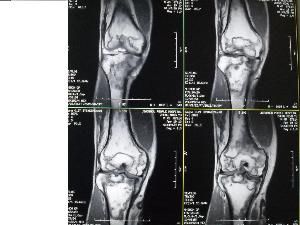

MRI表現 在骨梗死的不同時期其影像學表現也多種多樣。杜玉清等將骨梗死分為急性期、亞急性期和慢性期,其MRI表現分別為:(1)急性期:病變中心T1WI呈與正常骨髓等或略高信號,T2WI呈高信號,邊緣呈長T1、長T2信號;(2)亞急性期:病變中心T1WI呈與正常骨髓相似或略低信號,T2WI呈與正常骨髓相似或略高信號,邊緣呈長T1 、長T2 信號;(3)慢性期:T1WI 和T2WI 均呈低信號。以上分期和本組的早、中、晚期相對應。